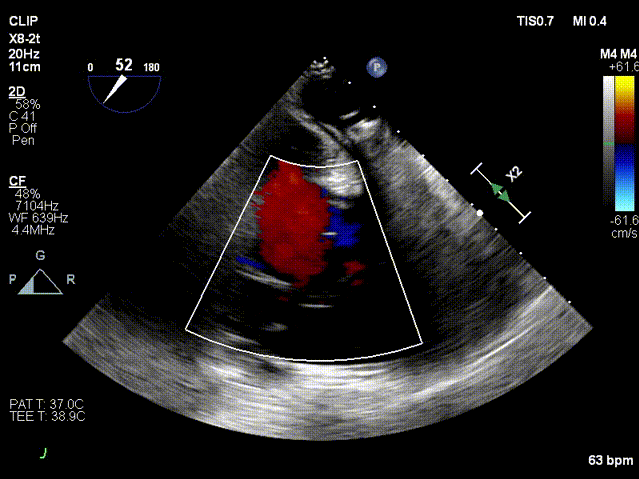

术前超声

术后超声